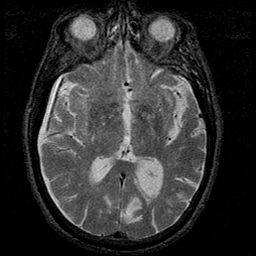

Subdural Hygroma,overlay -- Slice #23

[Home][Help][Clinical] Slice 23